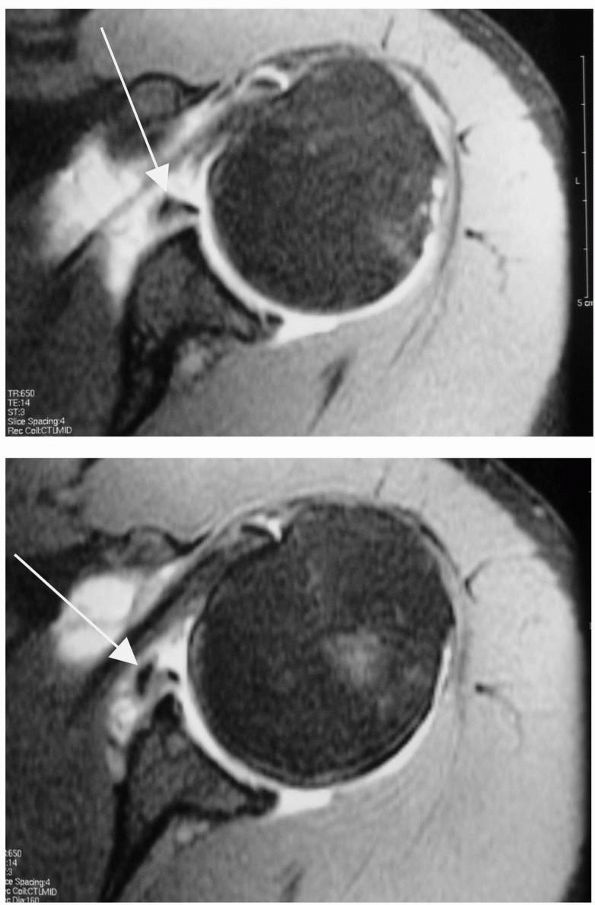

may develop significant contractures impairing activities of daily

living. Upper-trunk lesions result in weak external rotators against

intact internal rotators and adductors; this imbalance may lead to

posterior glenohumeral subluxation or dislocation with secondary

glenohumeral changes. In an attempt to avert this complication, a

subscapularis muscle slide has been described to increase passive

external rotation at 1 year of age for those unresponsive to physical

therapy.

contracture, external rotator and abductor weakness, and posterior

glenohumeral subluxation without significant glenoid deformity, the

Sever-L’Episcopo procedure has been successfully performed to address

the anterior contracture in addition to providing active external

rotation. First, open release of the anterior capsule with division of

the subscapularis and pectoralis major increase passive external

rotation. Second, transfer of the teres major and latissimus dorsi

tendons to the rotator cuff permits active external rotation.

and posterior glenoid is present from chronic subluxation or

dislocation, a derotational osteotomy of the proximal humerus becomes a

reasonable option. A transverse osteotomy is performed followed by

external rotation of the distal segment to improve the utility and

function of the existing arc of motion by rotating it into a more

central position.